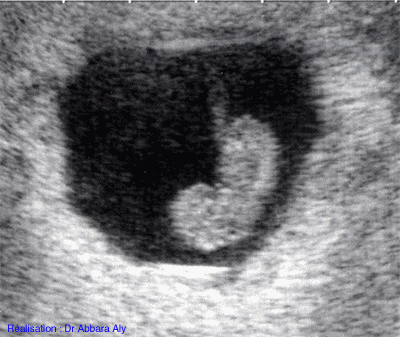

Embryon de 22 mm de longueur crânio-caudale

soit 9 semaines d'aménorrhée